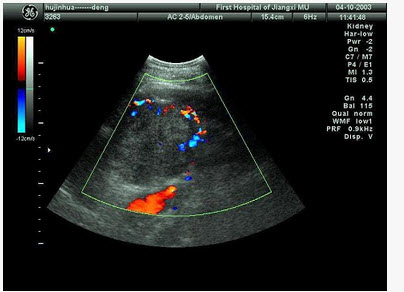

某患者肝脏发现肿块回声,根据CDFI声像图表现,最可能的诊断是()

A、肝血管瘤

B、肝脓肿

C、肝炎性假瘤

D、肝囊肿

E、肝癌

正确答案:

E